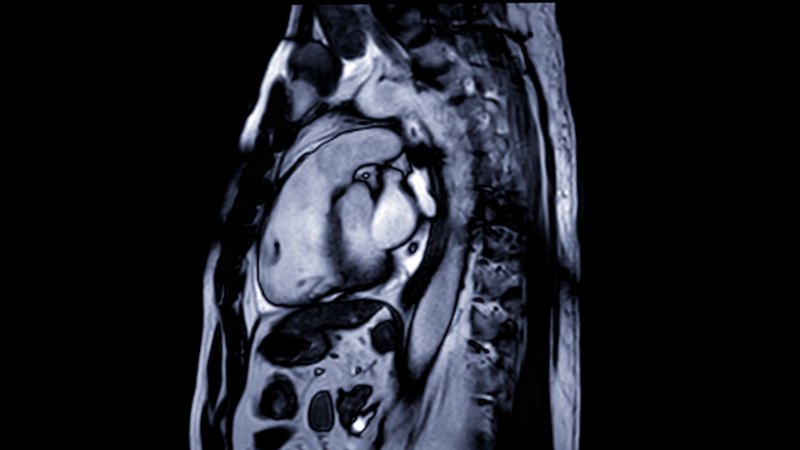

Cardiac magnetic resonance imaging (MRI) is another noninvasive diagnostic study that is often used if the results of previous diagnostics are unclear. This study uses magnets, radio waves, and computers to develop detailed imaging of the heart and its surrounding structures. Cardiac MRIs are especially beneficial in detecting inflammation or scarring of the heart.